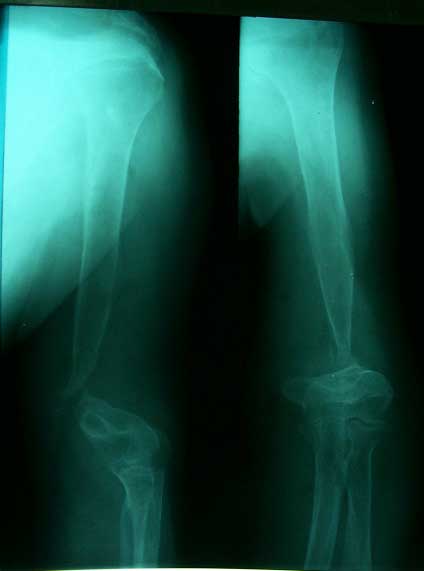

15岁,男。股骨骨母细胞瘤       肿瘤段截,异体骨植骨内固定,术后7年,正常生活。